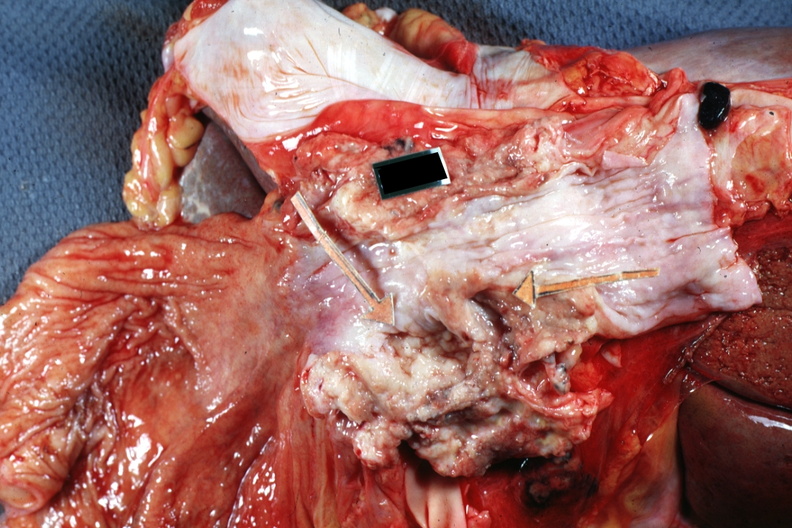

GROSS: GASTROINTESTINAL: Esophagus: Carcinoma: Gross natural color opened esophagus with stomach showing large ulcerative carcinoma in esophagus just above gastric junction